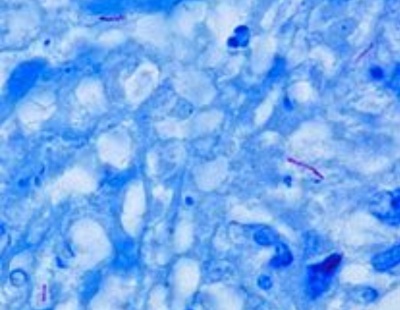

برای آشنایی با باکتری مایکوباکتریوم توبرکلوزیس این مطلب را تا انتها مطالعه کنید..........